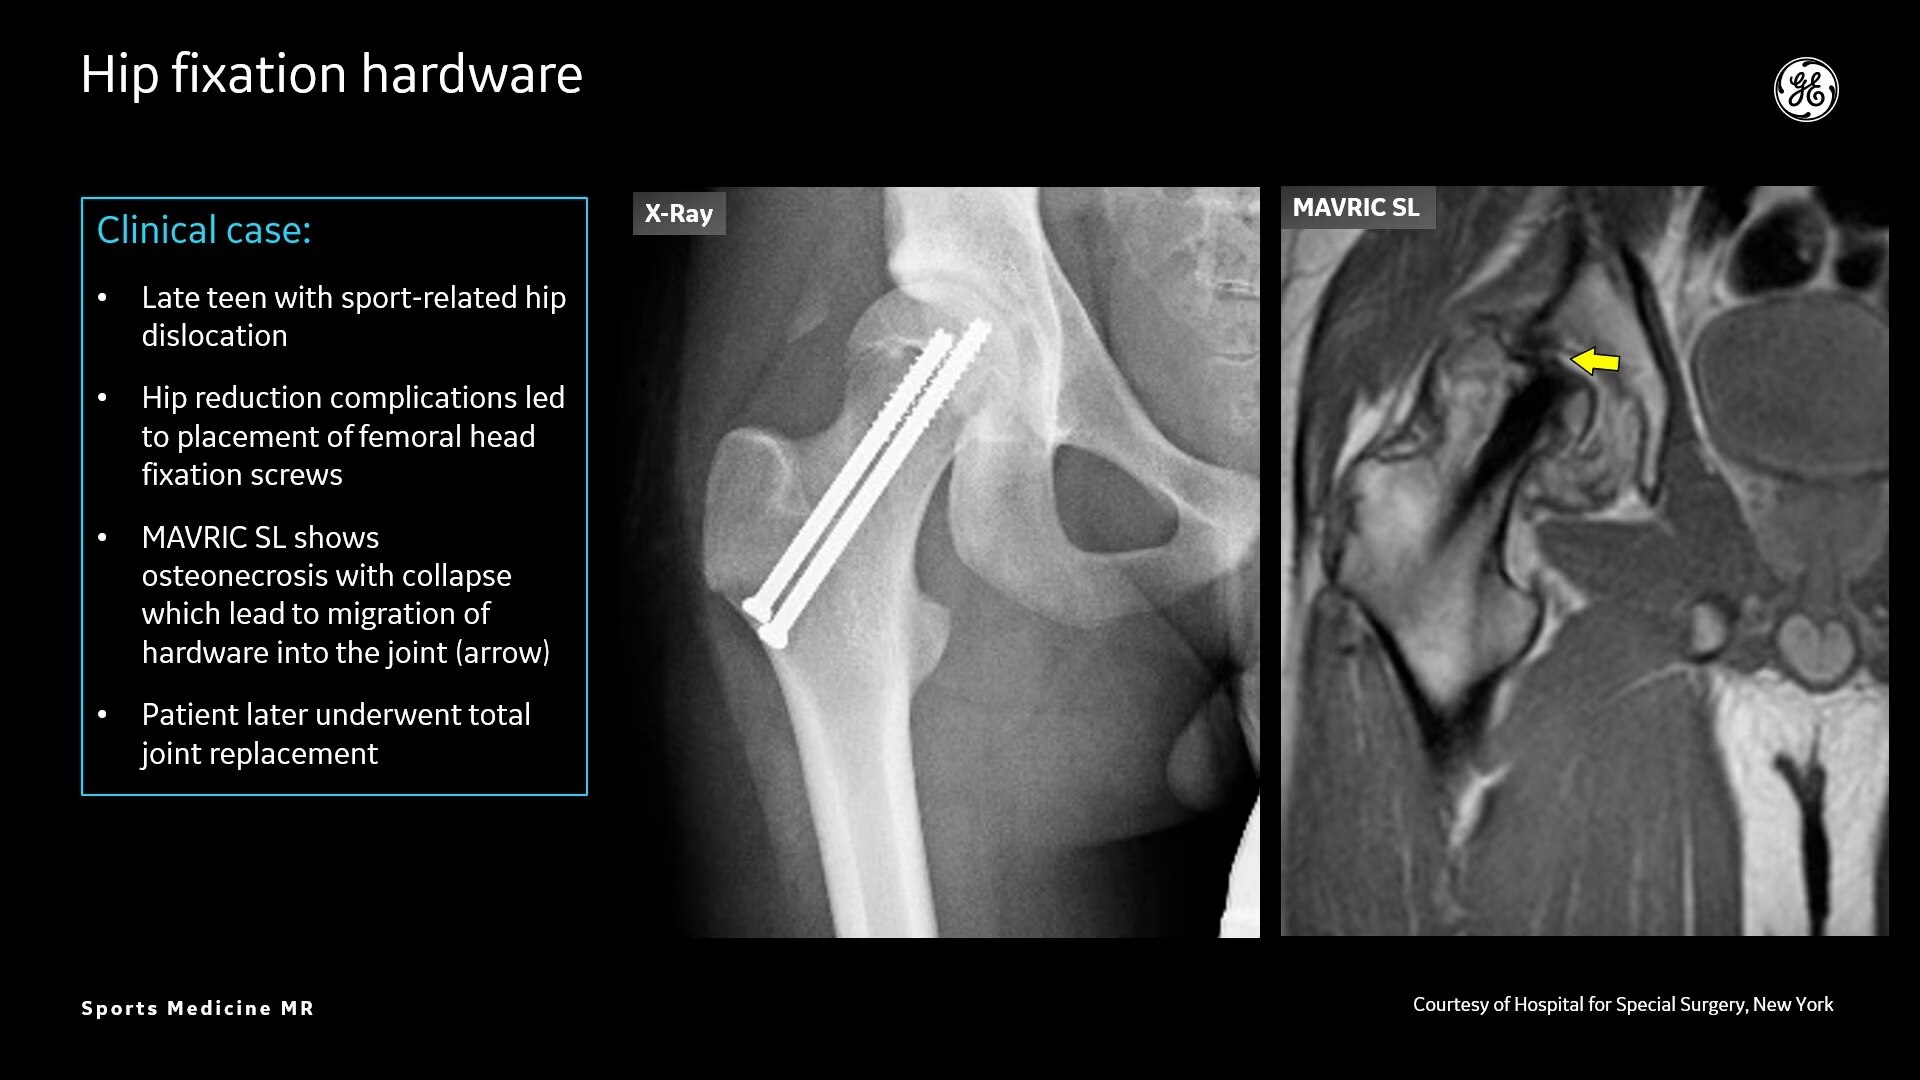

Sports Medicine Imaging

MR technology can scan both soft-tissue and bone injuries, all perfectly co-registered

AIR™ Recon DL provides high-resolution images with increased SNR at markedly reduced scan times. This technology optimizes the depiction of even small injuries, such as meniscal, labral and ligament tears. The reduction in scan times increases flexibility for individually tailored MR protocols with an additional oZTEo sequence for detailed fracture assessment.